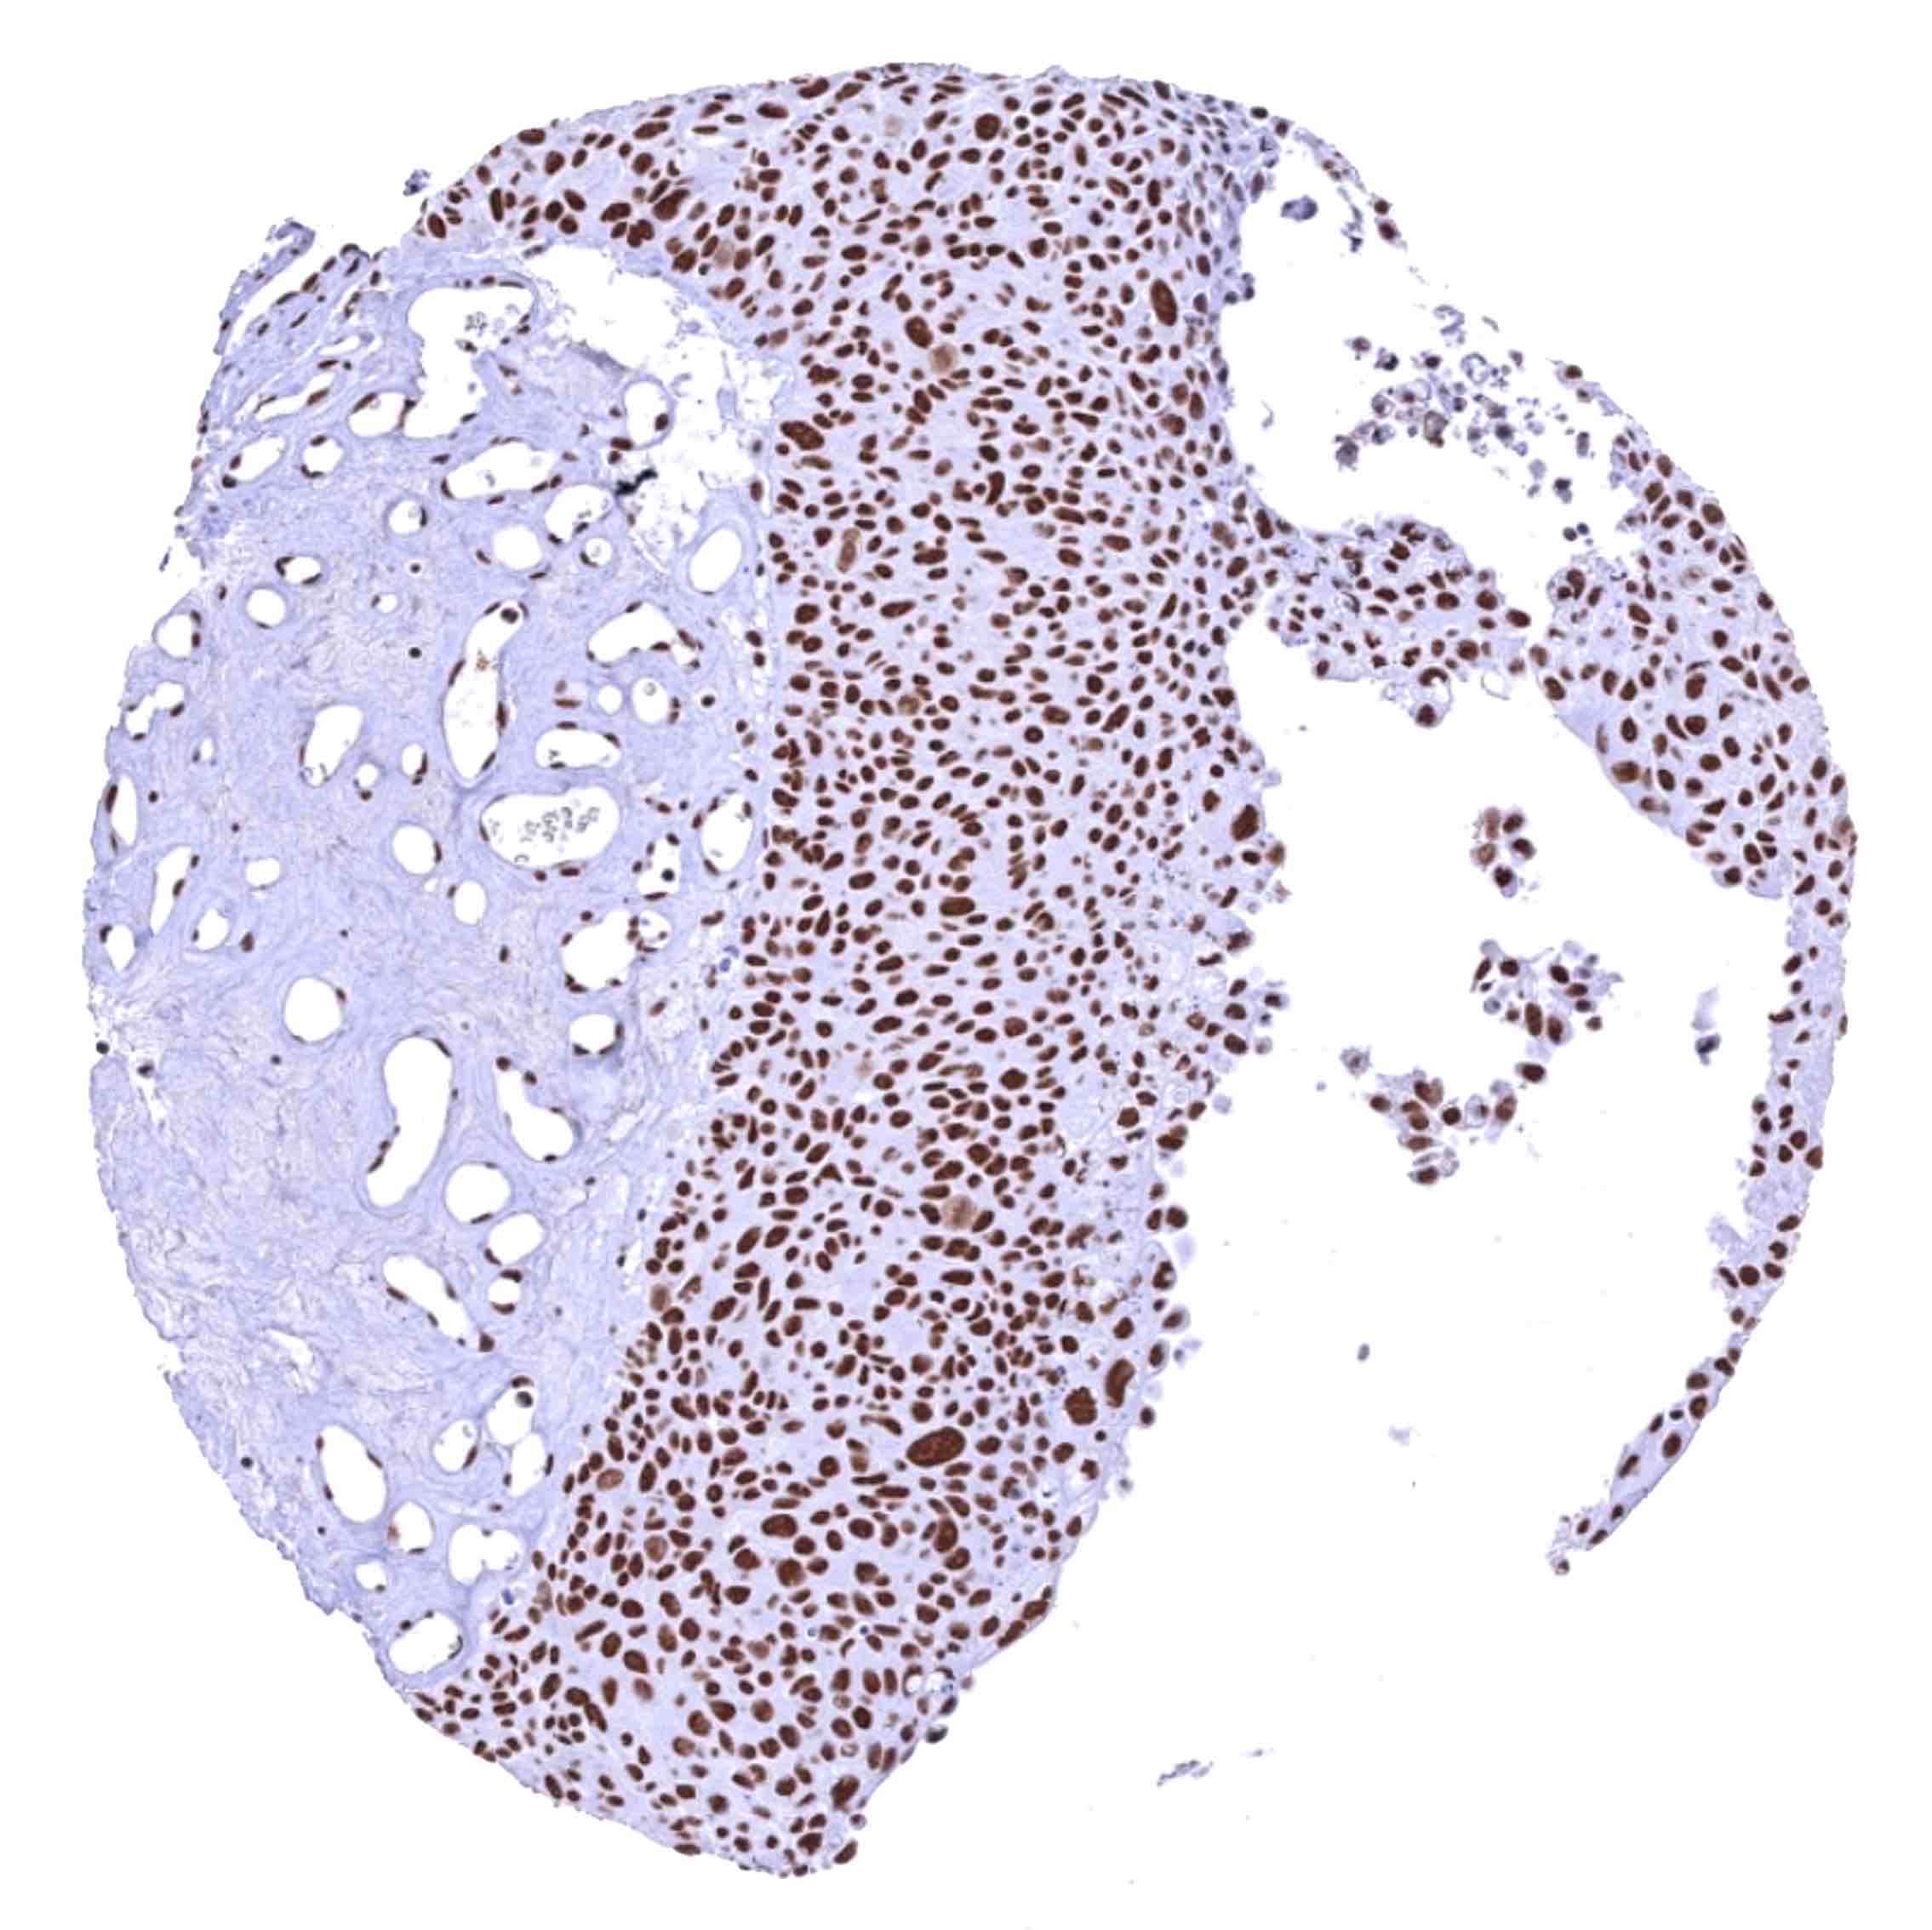

Urinary bladder – Muscle-invasive urothelial carcinoma with intense BRD4 staining of all tumor cells.